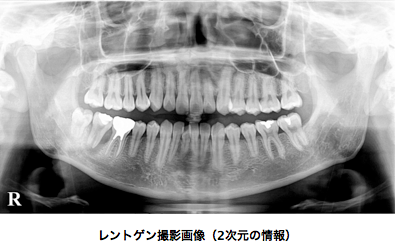

当院では、コンピュータ断層撮影(Computed Tomography、略:CT)機械を完備しています。 レントゲン撮影では2次元の情報しか得ることができませんが、CT撮影をすることで3次元の情報を得ることができます。安全安心の矯正治療を提供するにあたり、CT撮影(検査)は不可欠の検査であると当院は認識しています。

*レントゲン撮影では、歯茎の中に隠れた歯や骨の状態を把握することができます。